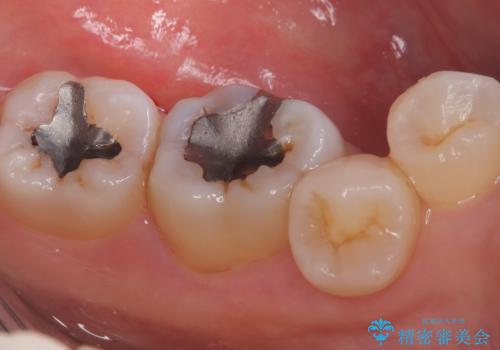

- 主訴:口を開けると所々入っている銀の詰め物が目立つので白い物にやり替えたい。

下顎大臼歯部に入っている保険適用のメタルインレーを、適合性と審美性の良いセラミックインレーでのやり替えとなりました。

メタルインレーを除去した際、古い裏層材やカリエスは除去し新たにCR裏層しています。